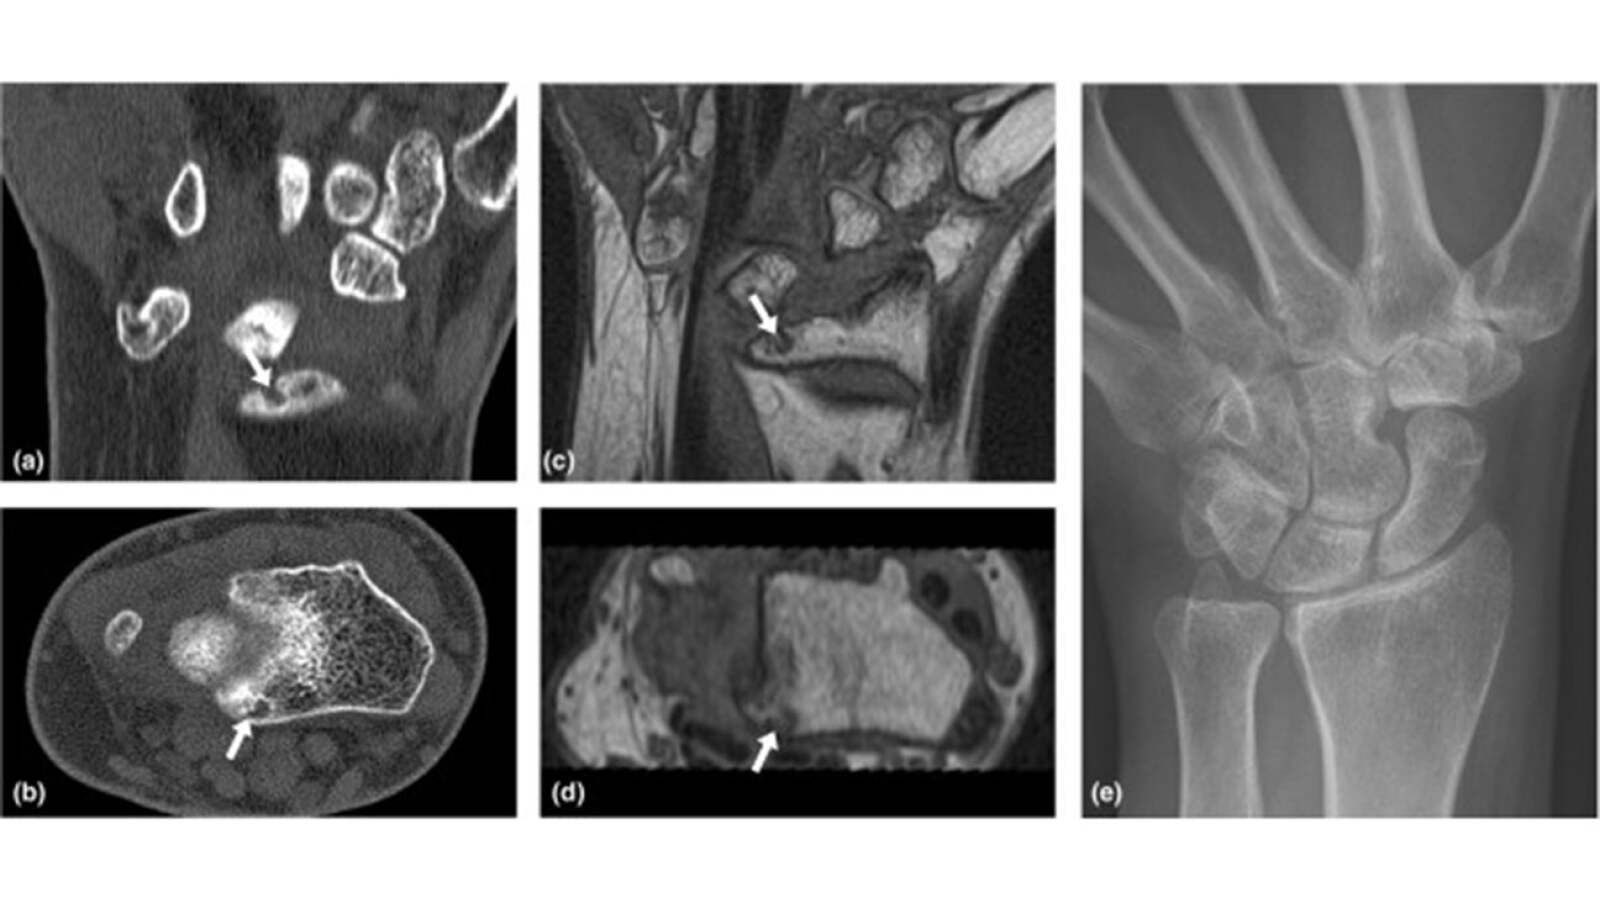

From www.hand.theclinics.com

Wrist Arthritis and Arthrodesis Hand Clinics What Can You Do For Wrist Arthritis Osteoarthritis (oa) is a degenerative joint disease that can cause pain, stiffness, and limited range of motion. Having painful arthritis in your wrist can make it hard to do many everyday activities. The wrist is made of many bones. An accurate diagnosis is crucial to. Wrist pain can be caused by many types of problems, ranging from sprains to arthritis.. What Can You Do For Wrist Arthritis.

Wrist Arthritis and Arthrodesis Hand Clinics What Can You Do For Wrist Arthritis Oa can affect any joint, including the. Osteoarthritis (oa) is a degenerative joint disease that can cause pain, stiffness, and limited range of motion. An accurate diagnosis is crucial to. The wrist is made of many bones. Wrist arthritis symptoms, such as inflammation and reduced mobility, may be similar to. Wrist pain can be caused by many types of problems,. What Can You Do For Wrist Arthritis.

Wrist Arthritis and Arthrodesis Hand Clinics What Can You Do For Wrist Arthritis Oa can affect any joint, including the. In the forearm there are two long bones (radius and ulna). Wrist arthritis is the loss of cartilage between wrist bones. An accurate diagnosis is crucial to. Wrist arthritis symptoms, such as inflammation and reduced mobility, may be similar to. Having painful arthritis in your wrist can make it hard to do many. What Can You Do For Wrist Arthritis.